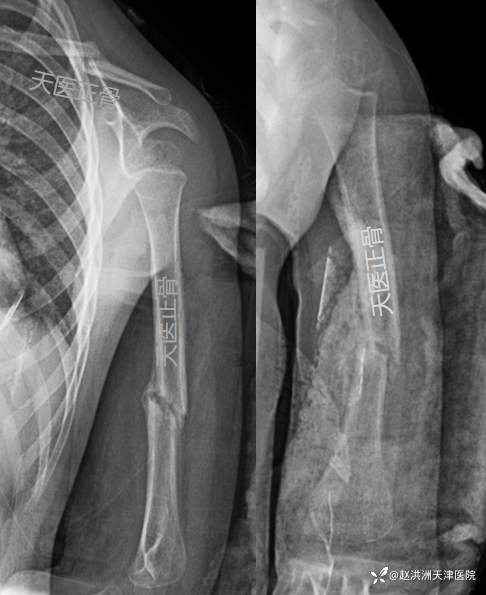

首诊X线片:左锁骨骨折+肱骨干骨折,重叠移位

复位后:肱骨对位可,残余轻度向外成角,锁骨重叠移位